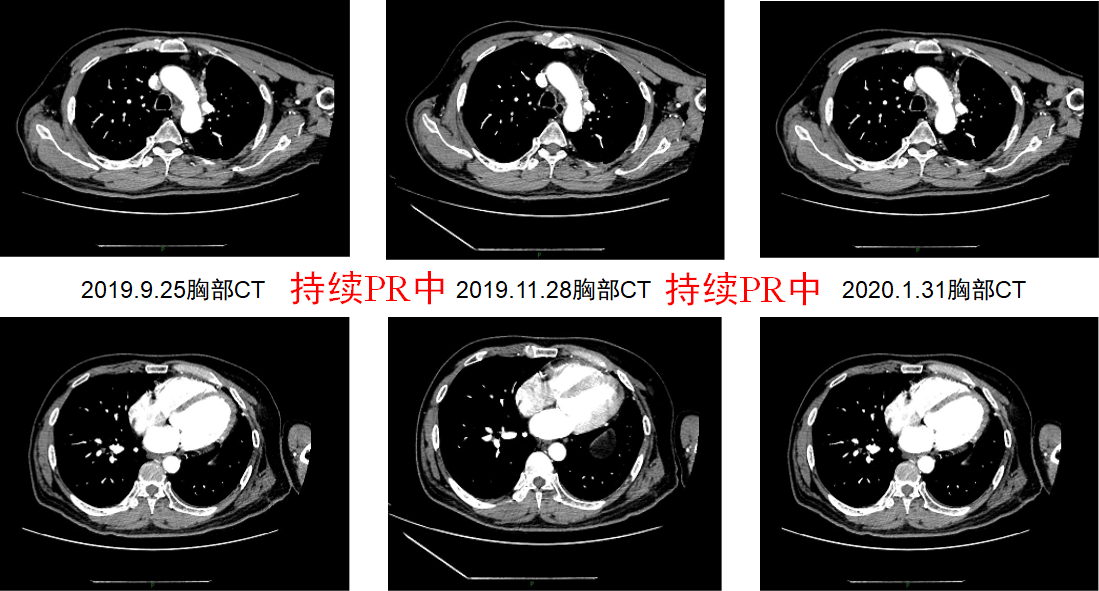

2018年10月16日起,患者接受信迪利单抗(200mg,d1)/安慰剂+吉西他滨(1650mg,d1,d8)+顺铂(122mg,d1)治疗4周期。用药2周期后,于2018年11月28日进行疗效评价为PR(图7)。期间患者出现Ⅱ度骨髓抑制,给予升白细胞等治疗后恢复。4周期治疗结束后,2019年1月12日再次进行疗效评价为PR(图8),治疗期间患者无明显不良反应。1月12日起,患者接受信迪利单抗(200mg,d1)/安慰剂维持治疗,共16周期,末次治疗时间为2020年2月3日,疗效PR(图9),PFS超过15个月,患者生活质量较前明显改善。维持治疗期间,患者每次输注临床用药后均有轻度的皮肤瘙痒症状,2-3天后缓解,考虑1级不良反应。

image015.png

图8.患者2019年1月和3月影像学资料

图9.维持治疗期间定期进行疗效评价,患者肿瘤持续PR中